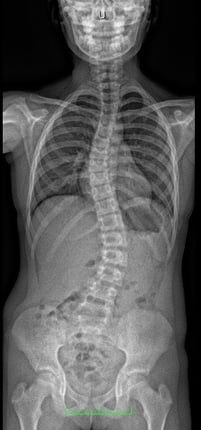

Die meisten Skoliosen entstehen und verschlechtern sich während Zeiten verstärkten Körperwachstums, wie zum Beispiel in den pubertären Wachstumsschüben. Da Skoliosen zunächst kaum bis überhaupt keine Beschwerden verursachen, bleiben sie oft lange unentdeckt. Bei jungen Patienten wird die noch vorhandene Formbarkeit der Wirbelsäule genutzt, um ein Maximum an Aufrichtung zu erreichen.